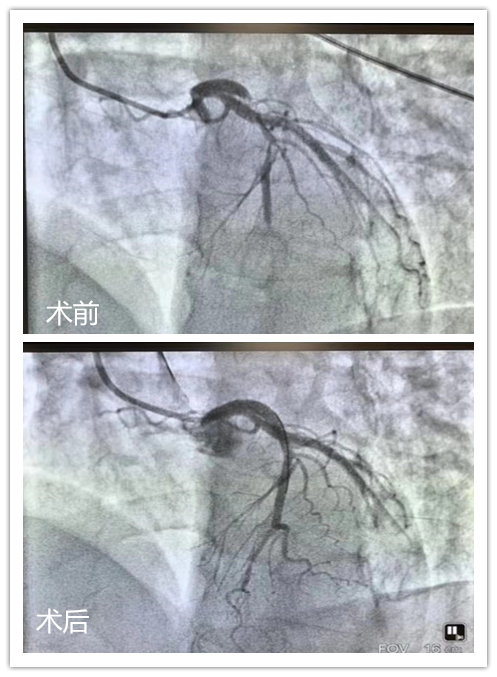

术中,可见患者左前降支急性闭塞,如果不打通这根犯罪血管,将随时有生命危险。心内五科罗巍副主任医师带领手术组立即对病变血管进行开通,植入支架一枚。术后,患者胸痛明显缓解。11月28日,许先生已经转至普通病房,并且喜笑颜开找到罗巍医师表示深深的感激。